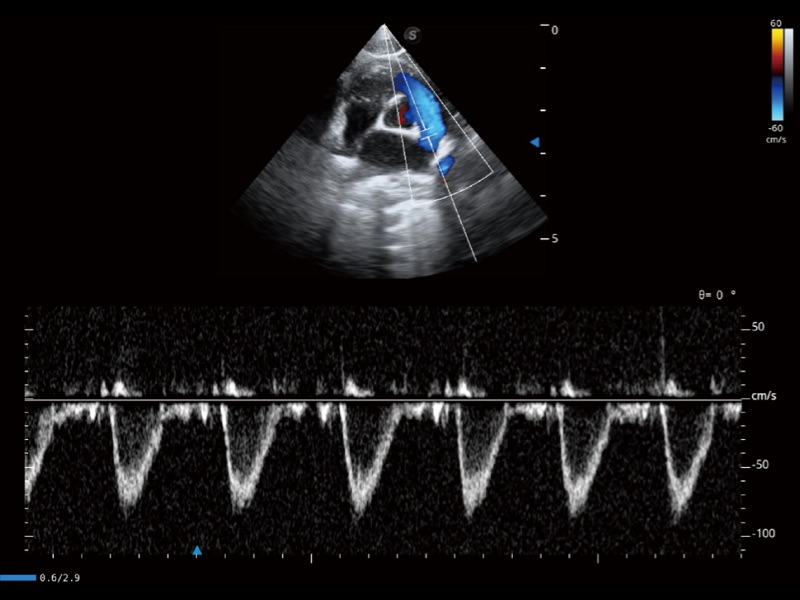

采用红、橙、黄、绿、青、蓝、紫这七种肉眼最为敏感的色彩,直观地显示组织内血流灌注的时间先后信息,更精准捕捉血流灌注走行细节。

通过创新的 Matrix E自适应滤波器和超长时间域算法,极大提升超低速微细血流的检出能力,同时更精准地滤除软组织和噪声信号,为兽用医生提供以往无法通过常规血流获得的疾病诊断信息。

通过色彩血流和实时宽景相结合,可观察到完整的静脉或动脉的血流,方便医生检查。实时扫查过程中,如有任何操作失误也可以很容易地进行回扫擦除,而不会中断扫查。